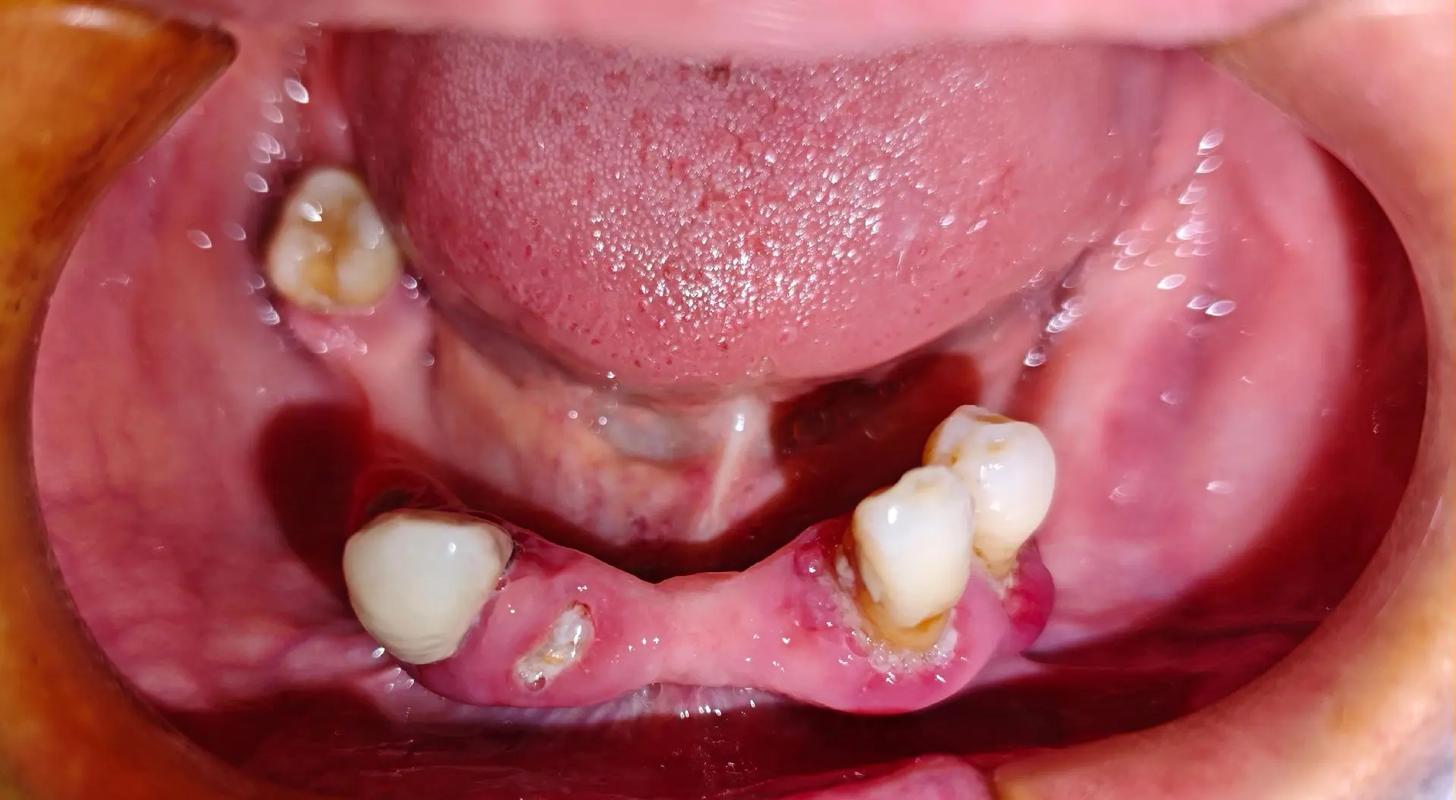

牙周炎患者的口腔环境存在慢性炎症,牙槽骨因炎症持续吸收,可能导致下门牙区骨量不足、骨密度降低,甚至出现骨缺损,若在牙周炎未得到控制的情况下直接种牙,种植体周围可能继发感染,引发种植体周围炎,表现为种植体周围牙龈红肿、溢脓、骨吸收加速,最终导致种植体松动脱落,牙周炎患者种牙的前提是彻底控制牙周炎症,通过系统治疗消除口腔内的感染因素,为种植体创造健康的“生存土壤”。

- 牙槽骨条件差:下前牙区牙槽骨厚度较薄(尤其是唇侧骨板),且骨高度常因牙周炎吸收而不足,易导致种植体初期稳定性不佳或术后唇侧牙龈凹陷。